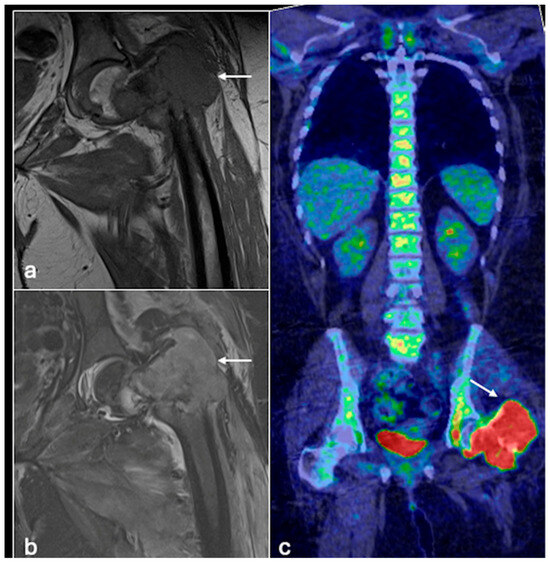

- Plaza de Las Heras, I.; García Cañamaque, L.; Quílez Caballero, E.; Camacho-Arias, M.; Cárdenas Soriano, M.D.P.; Martel Villagrán, J. Positron emission tomography-magnetic resonance imaging applications in pediatric musculoskeletal tumors. Quant. Imaging Med. Surg. 2024, 14, 7825–7838. [Google Scholar] [CrossRef] [PubMed] [PubMed Central]